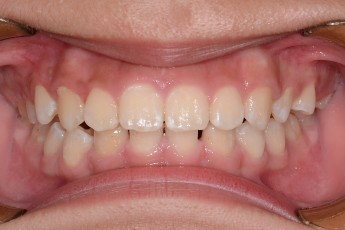

BEFORE & AFTER

- 덧니교정